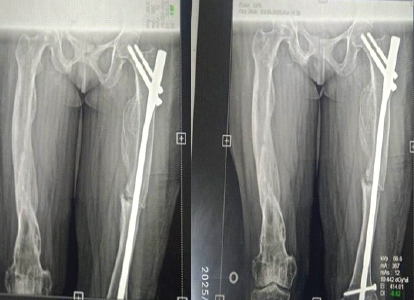

Patient pre-anesthetic evaluation workup was done and posted for surgery. The patient was placed supine on a fracture table, after standard painting and draping, and slight traction was applied. Moreover, closed reduction of the fracture was attempted and achieved under C-arm guidance. A small lateral incision was made proximal to the greater trochanter. An entry point was made at the tip of the greater trochanter under image guidance, and a guidewire was passed through the proximal femur into the shaft. Reaming was done over the guidewire sequentially. A long proximal femoral nail (PFN) (length: 28 cm, diameter: 9 mm) was inserted over the guidewire. Fracture alignment was confirmed under C-arm. 8 mm and 6 mm proximal locking screws were inserted through the jig. Distal locking was done using the freehand technique under C-Arm. Final fluoroscopy confirmed satisfactory fracture reduction, implant position, and screw placement. The wound was irrigated with saline, and hemostasis was ensured. Wound closure was done in layers. A sterile dressing was applied. The post-operative patient was allowed toe-touch with a Zimmer walking frame. Clinical and radiographic follow-up showed no displacement and consolidation after 8 weeks, and hence, full weight-bearing was started as tolerated. The patient was followed up after 5 months, and her physical status was almost comparable to the pre-operative level without any complications (Fig. 3, 4, 5, 6).

Figure 5: Partial weight-bearing X-ray after 3 months.

Figure 6: Full weight bearing after 5 months.